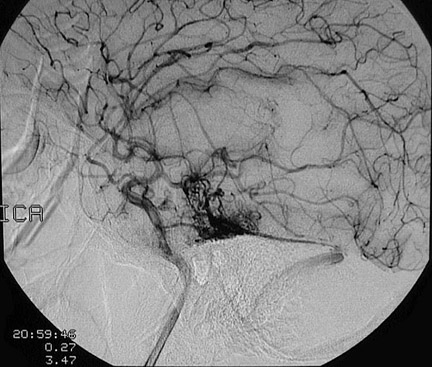

Click on the vascular malformation in the angiogram below:

This angiogram demonstrates a tortuous collection of irregular small vessels in the temporal region of the brain.